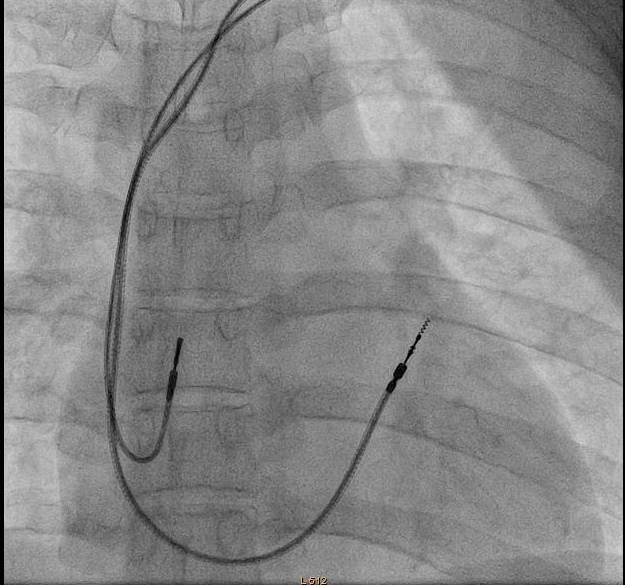

Confirm venous position

wires_ivc.jpg